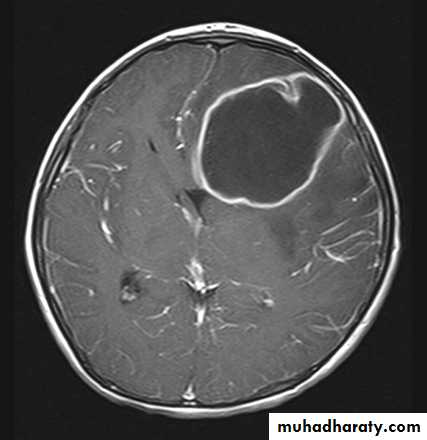

Is by C.T. scan with contrast which will show hypodense lesion surrounded by a ring of enhancement (the capsule) & oedema, MRI is not used as it takes a long time to achieve good result, a time which we don't usually have in patients with ICSOL as they are irritable and (unstable).Mastoiditis

CT scan of a brain abscess